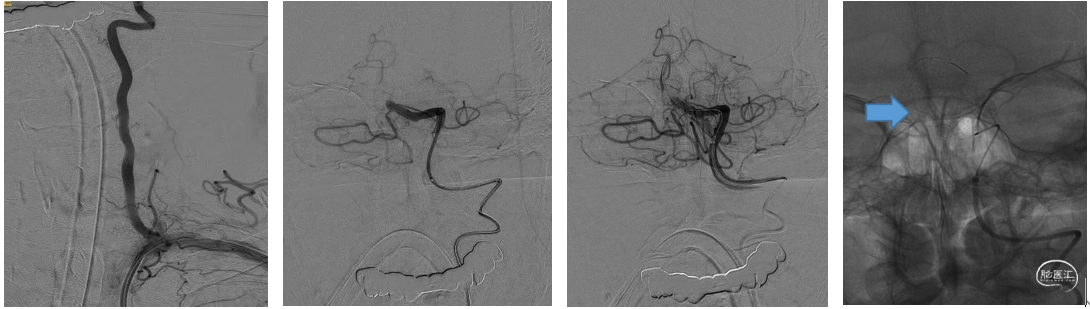

造影显示左侧椎动脉为优势血管,基底动脉闭塞部位呈笔尖征,结合临床症状提示ICAS病变(下图1、2)。首过效应阳性(下图3),释放4×30mm Syphonet®取栓支架,可见支架通体显影(下图4),支架中部呈现蜂腰征,辅助判断病变部位。

Syphonet®取栓支架释放后造影,可见前向血流部分恢复(下图1)。沿Syphonet®取栓支架的输送导丝推送2.5×15mm Maverick球囊至狭窄段,将取栓支架部分回收至球囊导丝腔(下图2)。

充盈球囊处理近端狭窄(下图1)。球囊泄压后前进中间导管越过病变(下图2)。

中间导管联合Syphonet®取栓支架进行远端取栓(下图1)。取出的血栓(下图2)。取栓后再次释放Syphonet®取栓支架,可见支架打开良好,蜂腰消失(下图3、4)。

造影判断血管再通良好,回收Syphonet®取栓支架,将微导丝置于远端等待观察(下图1、2)。术后情况:术后神志转清,左侧肢体肌力5级,右侧4级。